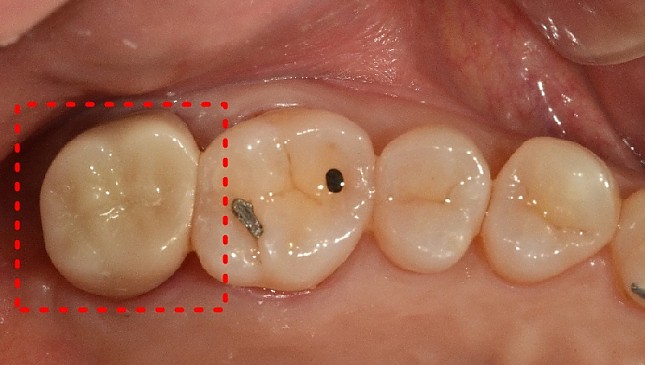

잇몸재생교정 치료 전후사진

잇몸 전체가 무너져 동시다발적으로 죽어가던 치아들을 한꺼번에 살려 냅니다.